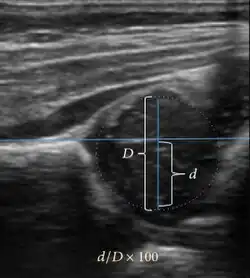

Ultrasound allows categorizing pediatric hips, according to Graf’s criteria, in four main types: normal, immature, and dysplastic (subluxed and dislocated). This classification is based on measurements of the acetabular inclination angle (alpha), cartilage roof angle (beta), and infant age. The femoral head coverage can also be determined by dividing the length of the femoral head covered by the acetabular fossa and the diameter of the femoral head. Its lower normal limits are 47% for boys and 44% for girls (Figure 11).[1]

Figure 11:

-

Useful ultrasound measures in neonatal hip sonography, alpha and beta angles.[1] -

Measurement of femoral head coverage.[1]